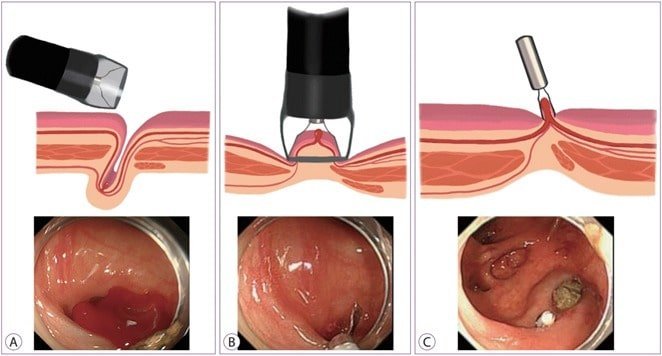

These are life-saving procedures often performed in emergency settings or as part of a regular de-varicealization program.